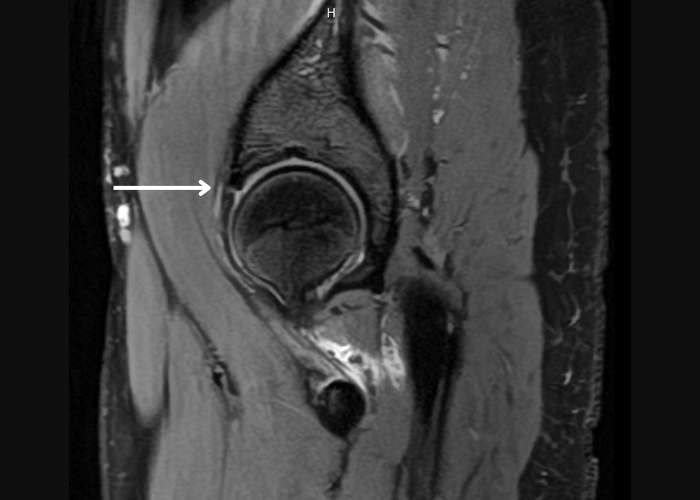

mri of hip labrum tear

How is a labral tear diagnosed?

Diagnostic imaging may include: